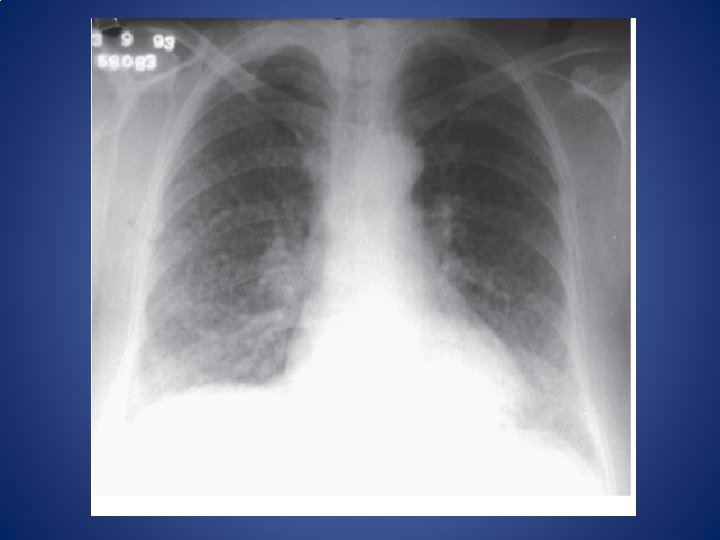

CASO CLÍNICO Paciente femenina de 67 años, fumadora empedernida desde la adolescencia. Se detectan

CASO CLÍNICO Paciente femenina de 67 años, fumadora empedernida desde la adolescencia. Se detectan signos de hipertensión pulmonar en la radiografía de tórax. • • Hallazgos semiológicos esperables Hallazgos fisiopatológicos esperables Hallazgos espirométricos esperables Hallazgos gasométricos esperables • Revisión de circulación pulmonar. Presiones. Efectos de la gravedad